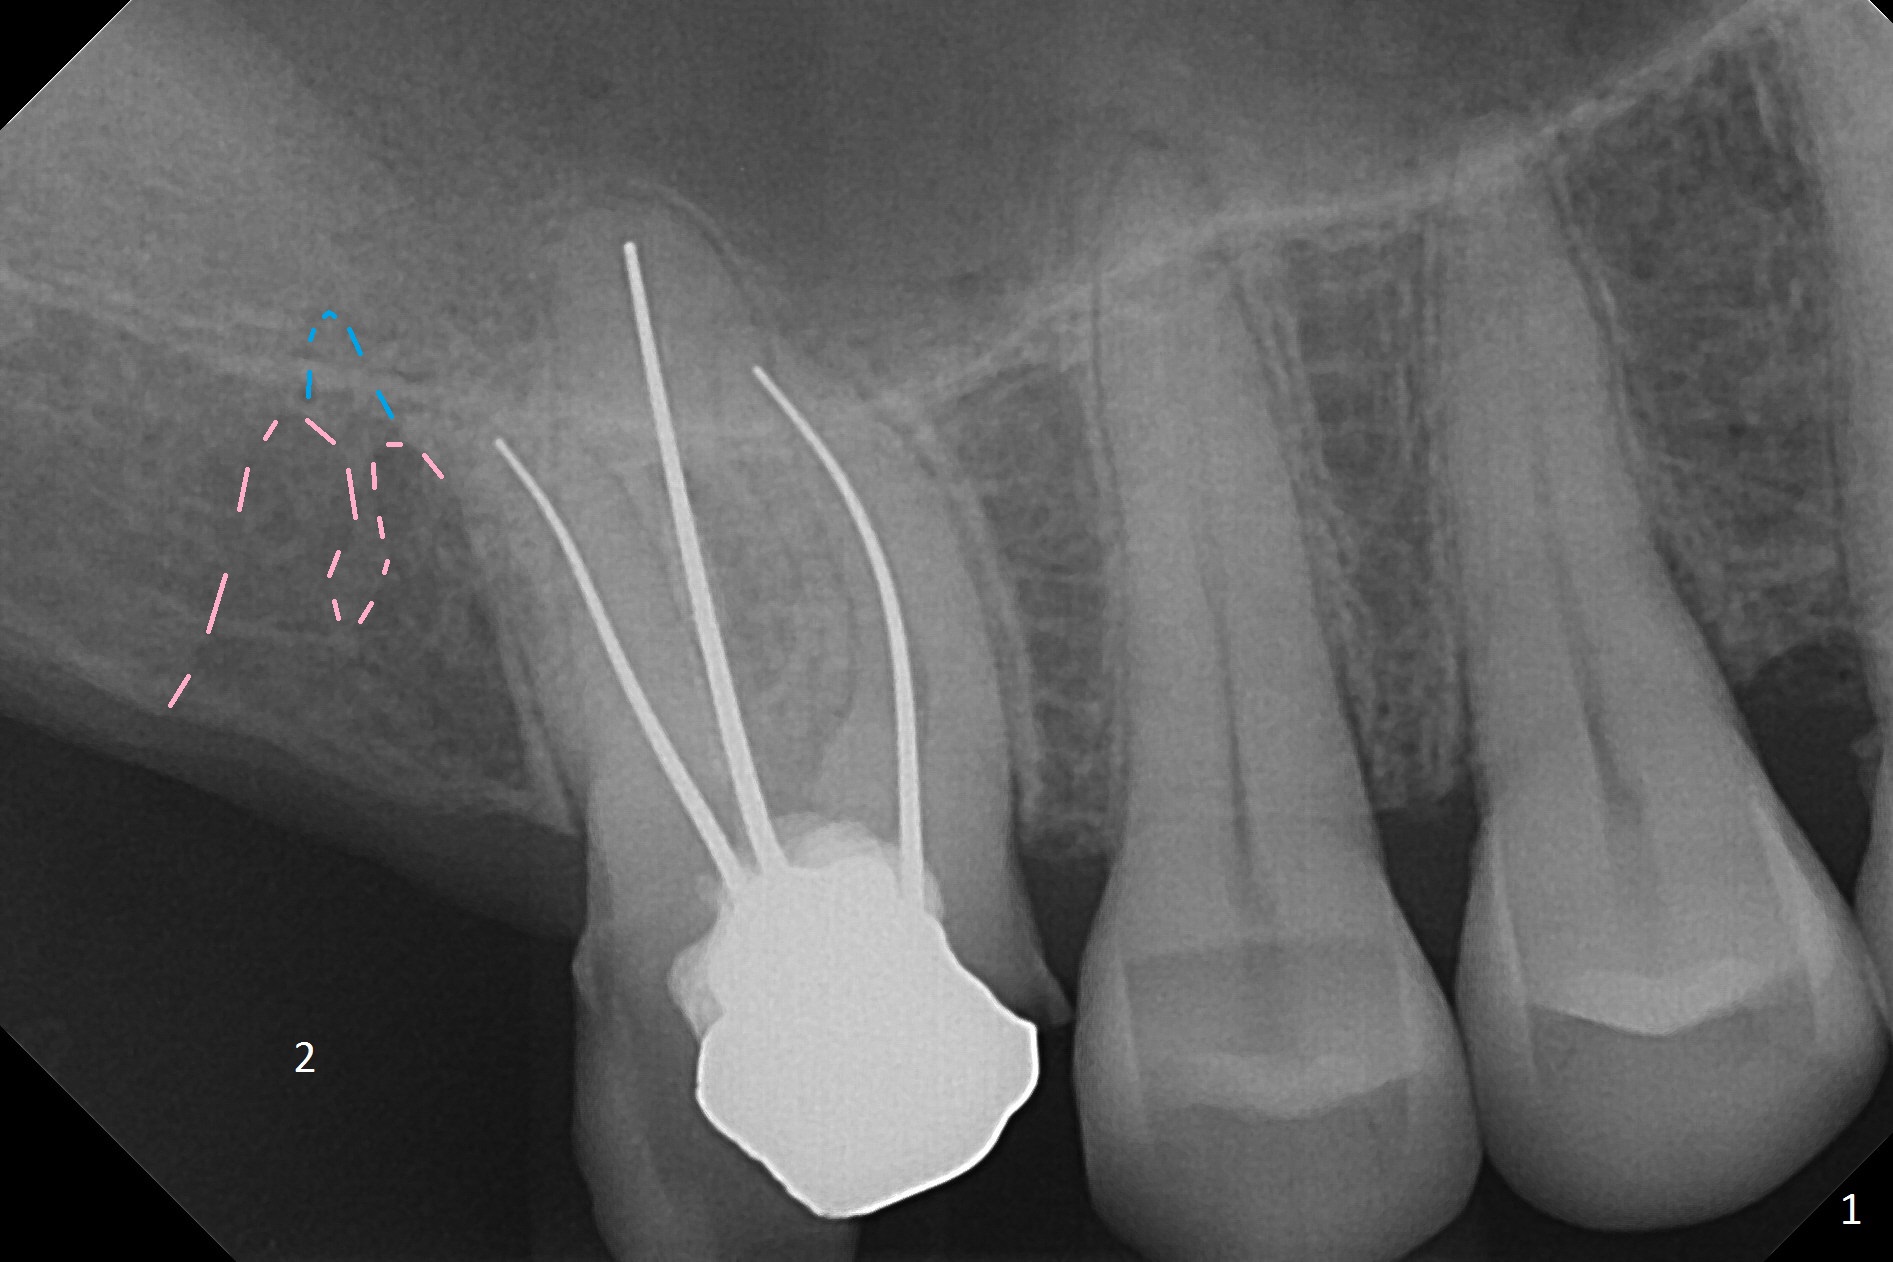

A 59-year-old man had #2 extracted approximately 4 months earlier (Fig.1 pink: possible buccal sockets; blue: palatal one). The edentulous ridge seems to be wide with exostosis (Fig.2 yellow line). Use Magic Split for access and initial bone expansion, followed by Magic expanders. The initial depth will be 7 mm to avoid sinus membrane perforation. Place PRF membranes and bone graft prior to inserting a 4 mm dummy implant. Periodontal dressing may be applied to the rugged surface of the tooth #3 for increased retention. Or a splinted provisional will be fabricated.